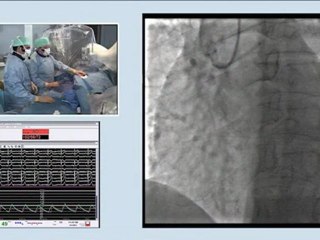

15 combined disease coronary artery stenting and left carotid artery stenting incathlab.com

Duration: 02:26